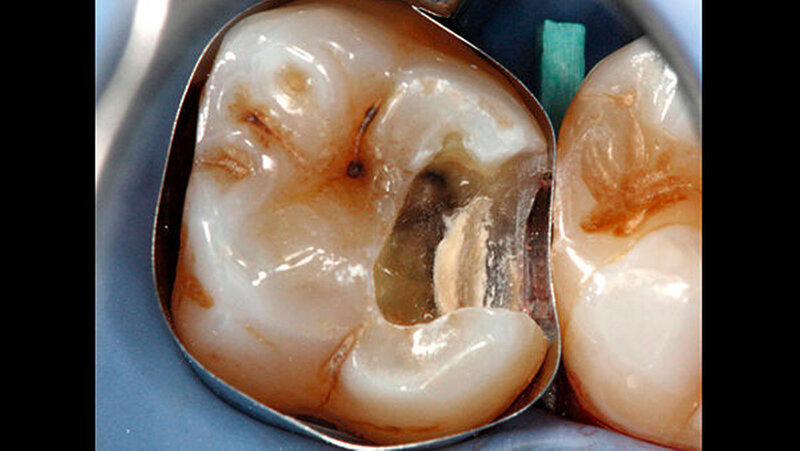

Das Zementmaterial wurde nach Herstellerangaben angemischt und mittels eines kleinen Kugelstopfers (Dycal-Instrument) im Bereich der distalen pulpalen Wand appliziert und mit einem Heidemann-Spatel adaptiert. Das Material wurde damit gleichzeitig sowohl zur Caries-profunda-Behandlung als auch zur Unterfüllung eingesetzt. Nach einer Abbindezeit für das Material von zwölf Minuten wurde der Defekt mit einer Kompositfüllung restauriert (Abbildung 4).